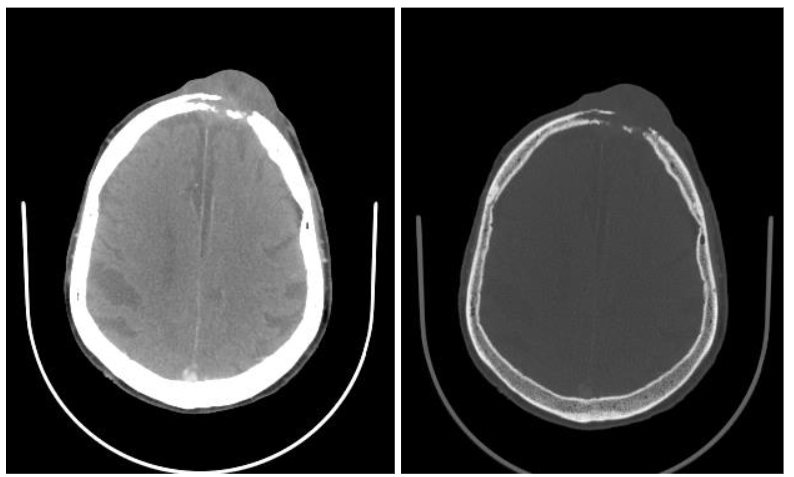

Computed Tomography

Computed tomography (CT) consists of cross-sectional scans created by combining X-ray images from different angles using computer processing. CT is especially helpful in assessing the degree to which skin lesions invade deeper tissues or organs. CT scans can accurately localize with a typical resolution of less than 1-2 mm, depending on the scan protocol. CT can quantitatively characterize the contents of lesions by measuring Hounsfield Units, which in turn can provide insights regarding the probable diagnosis. CT is especially useful for evaluating lesions that involve osseous structures, such as bone erosions from malignancy and infection, and for detecting calcifications. CT also excels at detecting the presence of gas and foreign bodies. Additionally, CT scans are relatively fast and accessible, which makes CT a convenient modality in emergency situations. Additionally, CT can be used to evaluate suspected deep extension of tumors and infections that may involve bone or soft tissues beyond what is visible in physical examination.